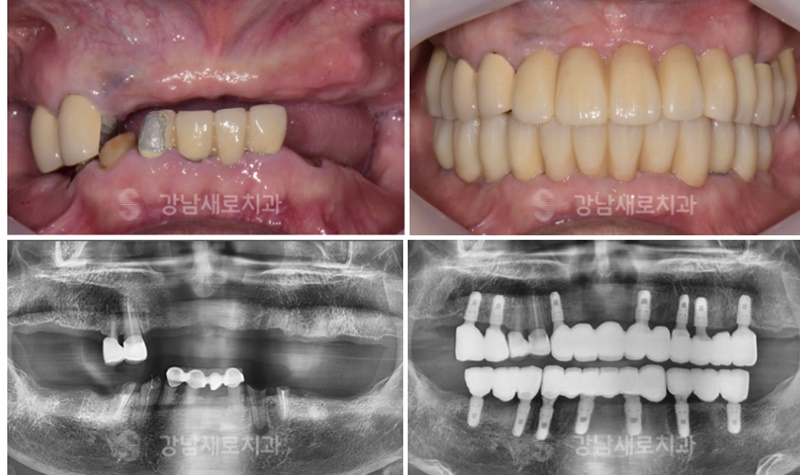

최소 식립으로 진행한 전체 임플란트 케이스

| 가장 적합한 위치에 꼭 필요한 임플란트만효율적으로 식립해야 더 오래 사용할 수 있고,치료 비용도 그만큼 줄어듭니다. |

없는 치아를 다 심을 필요 없이,

최소로 심어도 제대로 심어서

평생 씹고 편하게 드실 수 있도록

최소 식립 방식으로 안전하게

수술을 도와드리고 있는데요.